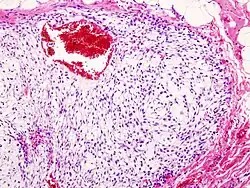

Kraakbeenkanker of chondrosarcoom is een kwaadaardige tumor die kraakbeen produceert. Het is een vorm van kanker die in wisselende mate van moeilijkheidsgraad te behandelen is. Zo kan het heel erg ingewikkeld zijn om de diagnose kraakbeenkanker te stellen. Het is vaak lastig om een onderscheid te maken tussen goedaardige en laaggradige kwaadaardige kraakbeentumoren. Kraakbeenkanker is een zeldzame vorm van kanker. Meestal zijn de patiënten ouder dan vijftig jaar. Hoe de ziekte ontstaat is nog niet bekend. Mensen met kraakbeenkanker hebben vaak veel pijn, dat komt door de mate van uitbreiding van de tumor of door verzwakking van het bot. Regelmatig wordt de kraakbeenkanker per toeval geconstateerd, na het maken van bijvoorbeeld een MRI of Röntgenfoto, dus zonder dat er duidelijke klachten zijn.

Net als bij andere vormen van kanker, is er bij kraakbeenkanker een kans op uitzaaiing. Deze kans op uitzaaiing is bij laaggradige chondrosarcomen zeer gering maar bij hooggradige chondrosarcomen is dat veel groter. Ditzelfde geldt voor de kans op lokaal recidief (terugkomen van de kanker op de behandelde locatie). Bij kraakbeenkanker zijn de vooruitzichten wisselend. Bij laaggradige chondrosarcomen is de prognose zeer gunstig, met een lokaal recidief kans op <5% en uitzaaiing <1%. Terwijl bij hooggradige chondrosarcomen dit veel hoger ligt: >20% lokaal recidief en >30% uitzaaiing. Chirurgie is vaak de enige manier om kraakbeenkanker te bestrijden, chondrosarcomen reageren bijna niet op chemotherapie en bestraling.